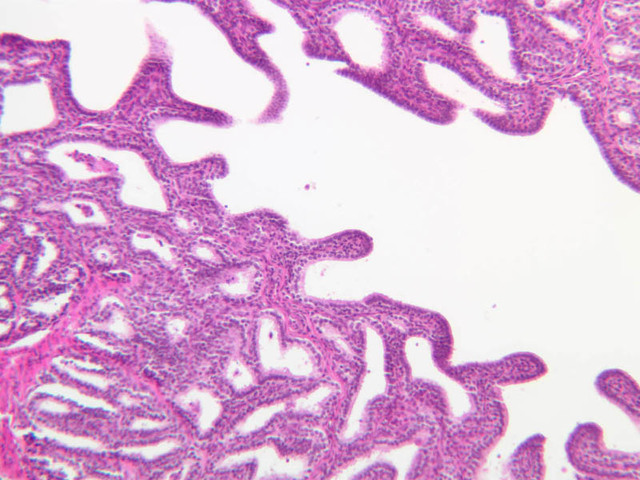

The seminal vesicles originate as diverticula of the ductuli deferentia. The duct of each seminal vesicle joins the associated ductus deferens a short distance before the latter empties into the prostatic urethra. With the scanning objective, note that the seminal vesicle appears to consist of several thick walled tubules lined with a secretory epithelium. Although the luminal lining is thrown into many folds and often appears cavitated, the cavities are not tubular glands, but freely connect with the central lumen. The epithelium, which rests on a vascular lamina propria, varies from low columnar to pseudostratified. The outer wall of the seminal vesicle is made up largely of an inner circular and an outer longitudinal layer of smooth muscle (slide B-89, H&E [2.5x, 10x-labeled, 20x, 40x] [2.5x, 10x, 20x, 40x-labeled] [2.5x, 10x-labeled, 20x, 40x]).